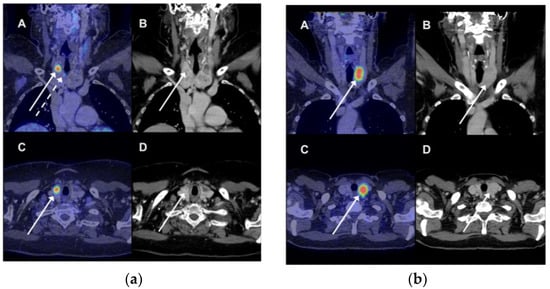

Among those 26 patients without follow-up, 21 (84%) patients had a diagnosis of cancer at the time of the PET/CT or was diagnosed with cancer during the follow-up period. Thirteen patients died from non-thyroid cancer within one year of the PET/CT. None of the 26 patients were diagnosed with thyroid malignancy at the end of the observation period. There was no follow-up for thyroid malignancy among the 2000 or more patients without FDG-avid thyroid lesions. Illustrative examples of focal FDG uptake are shown in Figure 1.

Figure 1.

(a) A 69-year woman had a 18F-fluorodeoxyglucose positron emission tomography/computer tomography (FDG PET/CT) scan because of suspected pancreatic cancer (not verified). There was incidental FDG uptake in three lesions in the right thyroid. The patient underwent total thyroidectomy; pathology showed papillary adenocarcinoma in all three PET-avid lesions. (A) Fused coronal PET/CT images showed intense FDG uptake (standardized uptake value, SUV 9.8) in the upper right part of the right thyroid (full white arrow). Another site of pathological FDG uptake was seen on this coronal slice as well (dotted white arrow). (B) The CT image showing a bilateral nodular goiter with an arrow indicating the site of most intense FDG uptake on the fused images. (C + D) Corresponding transverse images of the fused PET/CT images and CT scan with the most intense FDG-avid lesion; (b) An FDG PET/CT was performed in a 69-year woman due to suspicion of ovarian cancer (confirmed). Incidental FDG uptake was seen in the left lobe. A fine needle aspirate showed benign findings (colloid nodule). Any false-negative findings were ruled out during clinical and imaging follow. (A) Fused coronal PET/CT images showed intense FDG uptake (SUV 11.0) in the upper right part of the right thyroid (full white arrow). (B) The CT image showing a bilateral nodular goiter with an arrow indicating the most intense site of pathological FDG uptake on the fused images. (C + D). Corresponding transverse images of the fused PET/CT images and CT scan of the most intense FDG-avid lesion.